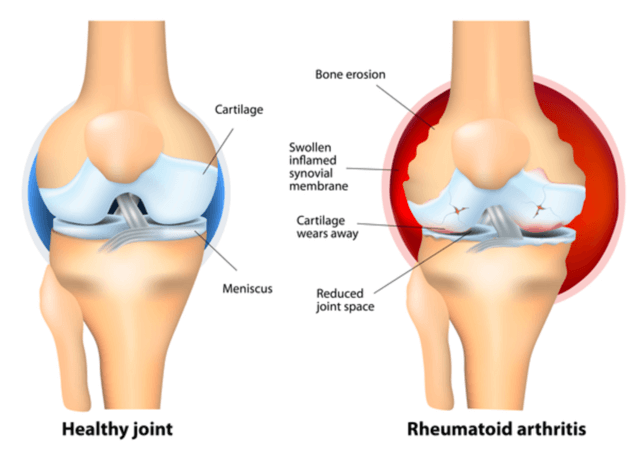

류머티즈, 즉 류머티즘 관절염은 주로 몸의 관절에 영향을 미치는 만성 염증성 질환입니다. 이 질병은 자가 면역체계 이상이 생겨 외부로부터 우리 몸을 지켜줘야 하는 면역체계에 이상이 생겨 우리 몸을 공격하면서 관절 주위를 둘러싸고 있는 활막이라는 조직의 염증을 발생시킵니다. 활막이 존재하는 모든 관절(움직일 수 있는 거의 모든 관절)에서 발생할 수 있습니다. 류머티즘 관절염 환자 연령층의 약80%가 30~60대에 발병하며 더러 유년기에 발병하는 경우도 있습니다. 남자보다 여자에 3-5배 더 많이 발생합니다.

류머티즘 관절염 관절염의 영향은 매우 심각하며, 사람 생활의 많은 측면에 영향을 미칠 수 있습니다. 관절에 심한 손상을 주어 변형이나 장애를 일으킬 수 있습니다. 관절통과 경직뿐만 아니라 류머티스 관절염은 폐와 혈관 등 몸의 다른 부분에 피로, 발열, 체중 감소, 염증을 유발할 수 있습니다. 류머티즘 관절염은 골다공증, 심장병, 감염병 등 다른 건강 문제의 위험도 높일 수 있습니다. 또한 정신건강에 영향을 미쳐 불안, 우울증, 사회적 고립으로 이어질 수 있습니다.